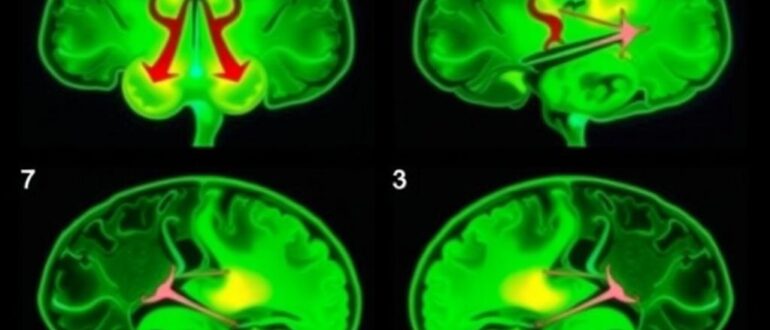

Интраоперационная нейронавигация: как это работает Интраоперационная нейронавигация — это система «путеводителя» для нейрохирурга во время сложных операций на мозге. Она соединяет данные предоперационного обследования с текущим положением инструментов

Нейромониторинг во время операции: защита функций Во врачебной практике нейромониторинг становится неким «пятим глазом» хирурга: он следит за работой нервной системы в реальном времени и помогает сохранить двигательные,